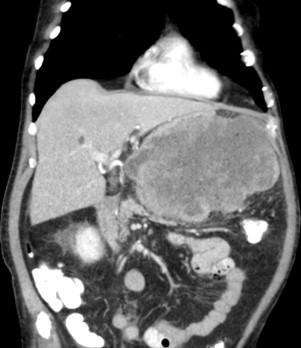

Giant retroperitoneal leiomyosarcoma. Multiorgan block removal.

67 years old man was admitted with back pain and fever. Abdominal imaging tests showed a 15cm abdominal mass without clear organodependencia. Endoscopy with biopsies evidenced mesenchymal neoplasia of undetermined origin. In surgery we confirm its resecability and was necessary multiorgan resection. Pathologic diagnosis: well differentiated retroperitoneal leiomyosarcoma. Started adjuvant radiotherapy. In subsequent tests showed the presence of liver metastases.